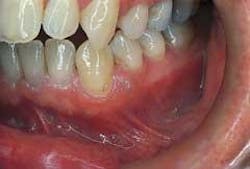

Intraoral examination revealed an elevated pinkish-translucent swelling on the attached gingiva between teeth #21 and #22 (see photo). The lesion appeared as a broad-based, compressible growth and measured approximately 0.5 centimeters in diameter. A smooth surface texture without ulceration or hemorrhage was noted. The teeth adjacent to the lesion were pulp tested for vitality and both teeth tested vital. Further examination of the oral soft tissues revealed no other masses present.